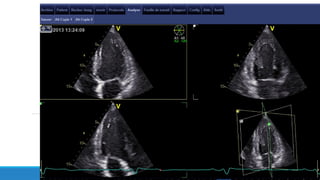

♣ Acquisition des images en 2D sur un cycle cardiaque

♣ Pour le strain global longitudinal: 3 coupes apicales: 3 cavités, 4C et 2C

Le 2D strain VG: acquisitions

Qualité de l’image ++

Acquisition apicale non raccourcie

Bonne qualité de l’ECG++

Bonne détection des QRS

Enregistrement sur 3 cycles incluant 100ms avant QRS

IPS 50-80 /s (en fonction de la FC)

Inclure tout le volume cavitaire (systole et diastole)

Pas de variations de la FC (FA3D strain ou cycles équivalents)